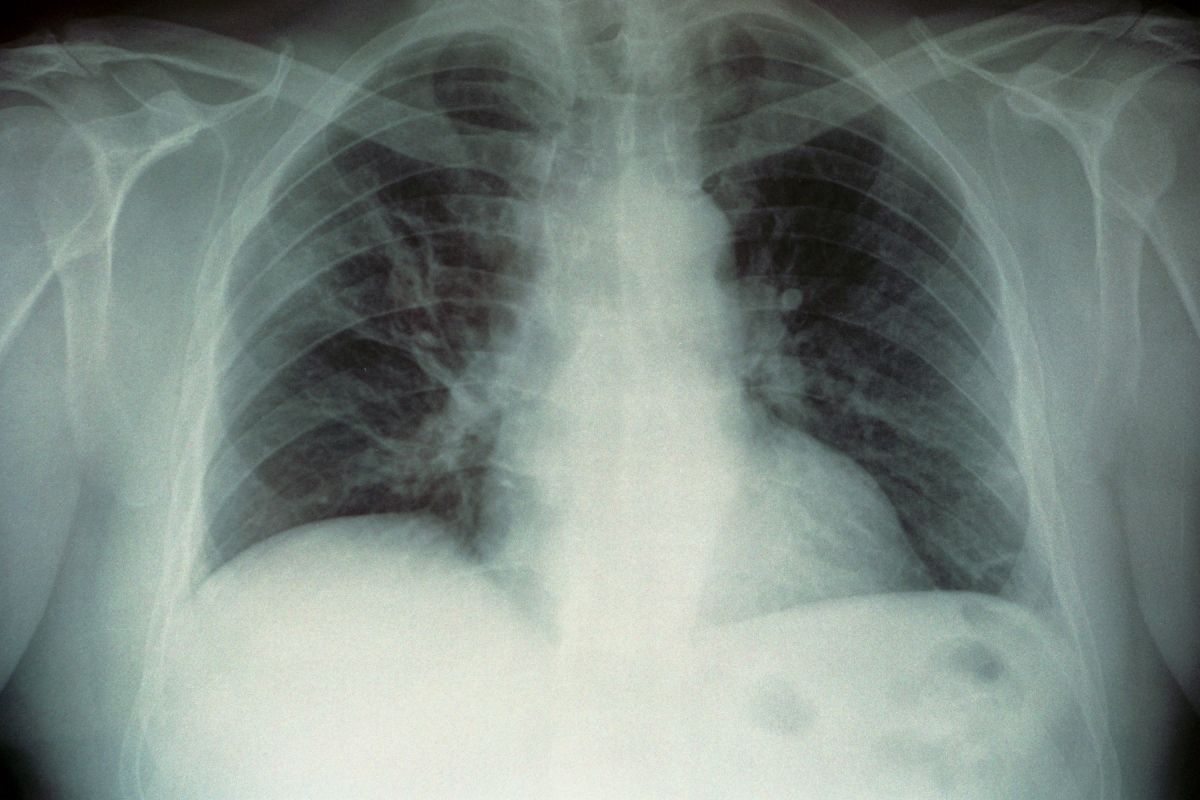

Huda oblika pljučnice

Legionarska bolezen, ki jo povzroča bakterija legionela, lahko namreč povzroči hudo obliko pljučnice, najpogostejša oblika prenosa pa je vdihavanje kontaminiranih vodnih kapljic.